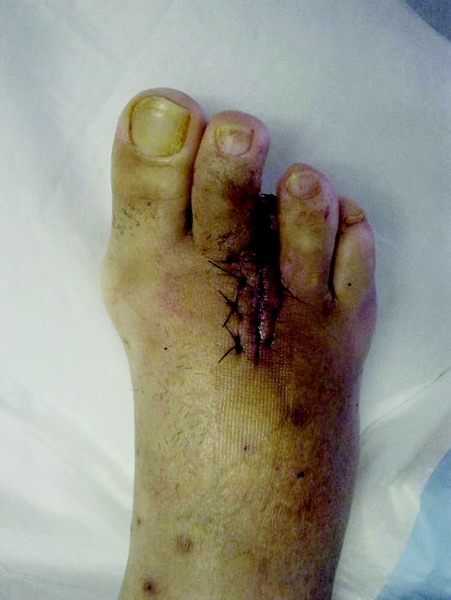

How Ulcerations Affect Planning For Amputations

While the presence of ulcerations guides the surgeon in the planning of incisions, it may not require a more proximal level of amputation. However, the existence of ulceration does require one to explore structures through which the ulcer extends. The surgeon must examine for non-viable tissue, infection, extension to bone and osteomyelitis. All of these represent tissues that may require excision. It is possible, though, to have an ulceration that has not progressed to the level that allows for deep infection. In that case, isolated remodeling of the ulceration can allow for a more distal amputation (more distal than the site of the ulceration), which is almost always preferable. Utilizing simple techniques of plastic surgery — rotation advancement flaps and pedicle flaps — one may remodel ulcers at the surface while leaving the structures below intact. One must consider the reality that one amputation can lead to another in the future due to the creation of biomechanical abnormalities or a worsening of disease. Given this possibility, one must perform initial incisions for an initial amputation in such a way as to avert difficult scenarios in future surgeries, if at all possible. The classic example is when one has to address an infected ulcer directly plantar to a metatarsal head. Often, surgeons may extend their incision from the metatarsal head to the proximal arch. If this presenting complaint subsequently becomes worse and progresses into an infected deep plantar space, the linear incision from distal to proximal through the arch may present the surgeon with a dilemma when he or she tries to convert this to a Loeffler and Ballard incision to view those compartments.14 This is the pitfall of seeing a problem in isolation when one knows the natural history of the amputation.2 For example, the natural history of the hallux amputation was well documented in the article by Murdoch, et. al., in The Journal of Foot and Ankle Surgery.15 In this retrospective study of 90 patients over a 10-year period, 60 percent of the patients had a subsequent second amputation, 21 percent had a third and 7 percent had a fourth. Seventeen percent underwent a below-the-knee amputation and 11 percent had a transmetatarsal amputation. There were also contralateral limb amputations with 3 percent below the knee and 2 percent undergoing transmetatarsal amputation. Therefore, it is obviously important that at each step of the way, surgeons should not plan any incisions that will limit their ability to complete the next procedure in an efficacious and skillful manner, preserving skin coverage and circulation.